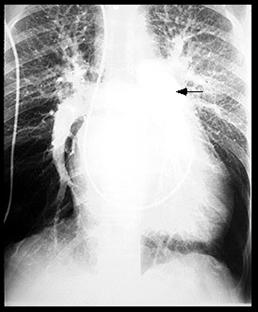

Rx cord-pulmon: circulatie pulmonara 'incarcata' cu ramurile AP dilatate in hiluri si extremitati 'retezate' avind periferie mult mai clara decat normal, bombare a conului arterei pulmonare, semne de hipertrofie VD

Imagine radiologica de HTPS (DVPA) Imagine radiologica de HTPS (stenoza mitrala)

HTP secundara incipienta (DSA) HTPS severa (DSA Eisenmengerizat)

Imagine Rx. de profil cu HVD Aspect CT de HTP primara